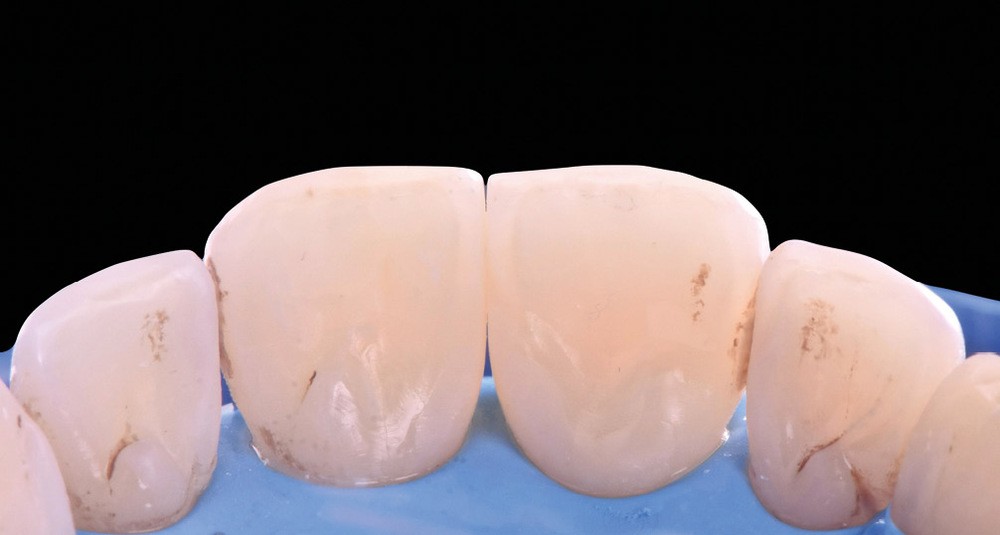

La fermeture des triangles noirs en technique directe avec des résines composites offre une alternative très favorable avec une approche non invasive, esthétique, un coût réduit et une possibilité de réintervention aisée. Plusieurs méthodes ont été proposées : réalisation à main levée sans matrice (à proscrire), avec bande de matrice transparente plate ou galbée, avec matrice postérieure customisée et utilisée verticalement… Il faut bien comprendre qu’aucun coin en bois ou plastique ne pourra être employé pour stabiliser cette matrice, car il empêcherait la création d’un profil d’émergence anatomique convexe en induisant une déformation concave de la matrice à sa base.